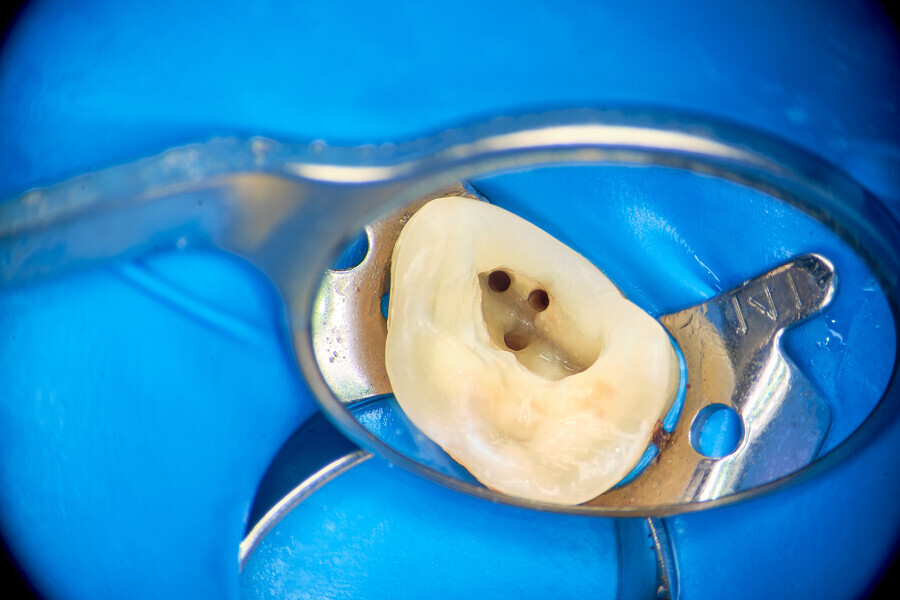

A 34-year-old patient was referred to our clinic for endodontic primary treatment. The patient had acute pain and was treated during an emergency visit. The initial radiograph (Fig. 26) and intra-oral examination demonstrated the need for endodontic intervention for tooth #16. The access cavity was created with the use of the ED3D ultrasonic scaler tip (Woodpecker) and adapted in order to visualise all of the pulp chamber floor (Fig. 27). A pulp stone was located and removed also with the ED3D tip (Figs. 28 & 29). Before instrumentation, initial irrigation of the cavity with 5.25% sodium hypochlorite and activation with EDDY tips was performed in order to remove remnants of the pulp from the pulp chamber (Fig. 30). The initial glide path was then created using manual ISO #8–10 K-files (VDW). Mechanical instrumentation with VDW.ROTATE files in the second mesiobuccal, first and second distobuccal, and palatal canals and the R25 RECIPROC blue file (VDW) was used in the first mesiobuccal canal (Fig. 31). All instruments were used in the in–out technique with copious irrigation with activation in between instruments. Owing to the very long and curved canals, the IrriFlex needle (PD) was used for the final irrigation protocol (Fig. 32). Obturation was done with VDW.1Seal using the cavit piston technique (Fig. 33). The final radiograph was taken and examined regarding the clinical outcome (Fig. 34). From the visible lateral anatomy obturation, it can be concluded that the in–out technique for use during preparation is a promising solution for clinical success in canal preparation.

Fig.: 27

Fig.: 28

Fig.: 29

Fig.: 30

Fig.: 31